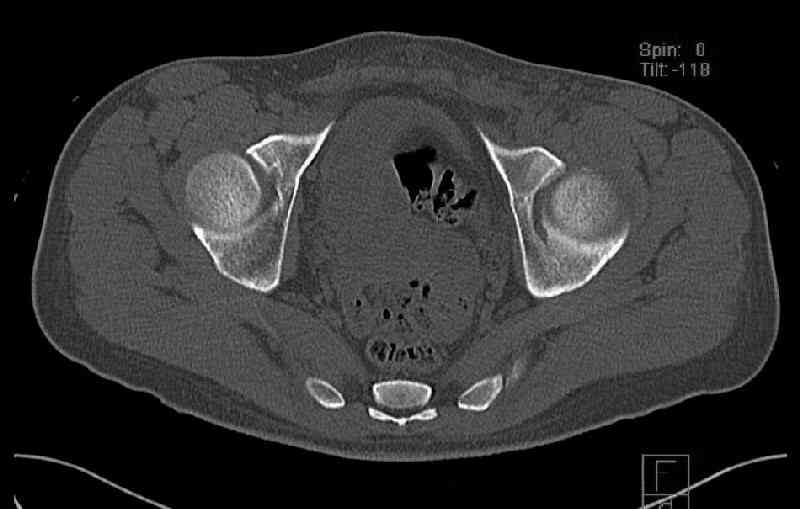

The last two images from the 3-D CT scan certainly makes the fracture look worse than the plan radiographs.

The joint is non-concentric as the head appears to be either "following the caudal segment", or the dome component is displaced from the tethered head... or so it seems... and he's young... so, many fracture surgeons would recommend reduction and fixation.

So we must decide preoperatively which part is the displaced segment?

It's difficult to know from these few selected images which component of the injury (was before and now) should be deemed the "soon to be mobile"

segment. It's my best guess that it is the caudal portion and there exists a healing fracture line somewhere thru the posterior column...one image

Some more images. Does it help to guess which part of the acetabulum is displaced?

Normal appearing SI joints and a healed posterior column limb... my bet's on caudal segment displacement.